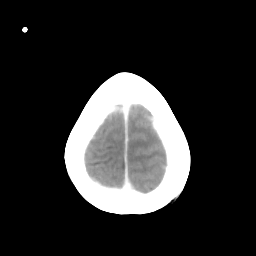

Metastatic bronchogenic carcinoma: Roentgen-ray CT -- Slice #20

[Home][Help][Clinical] Slice 20